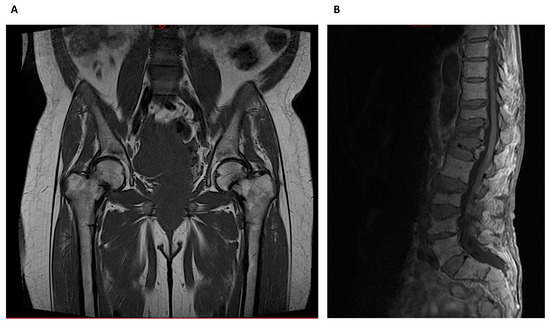

3.7. Magnetic Resonance Imaging (MRI)